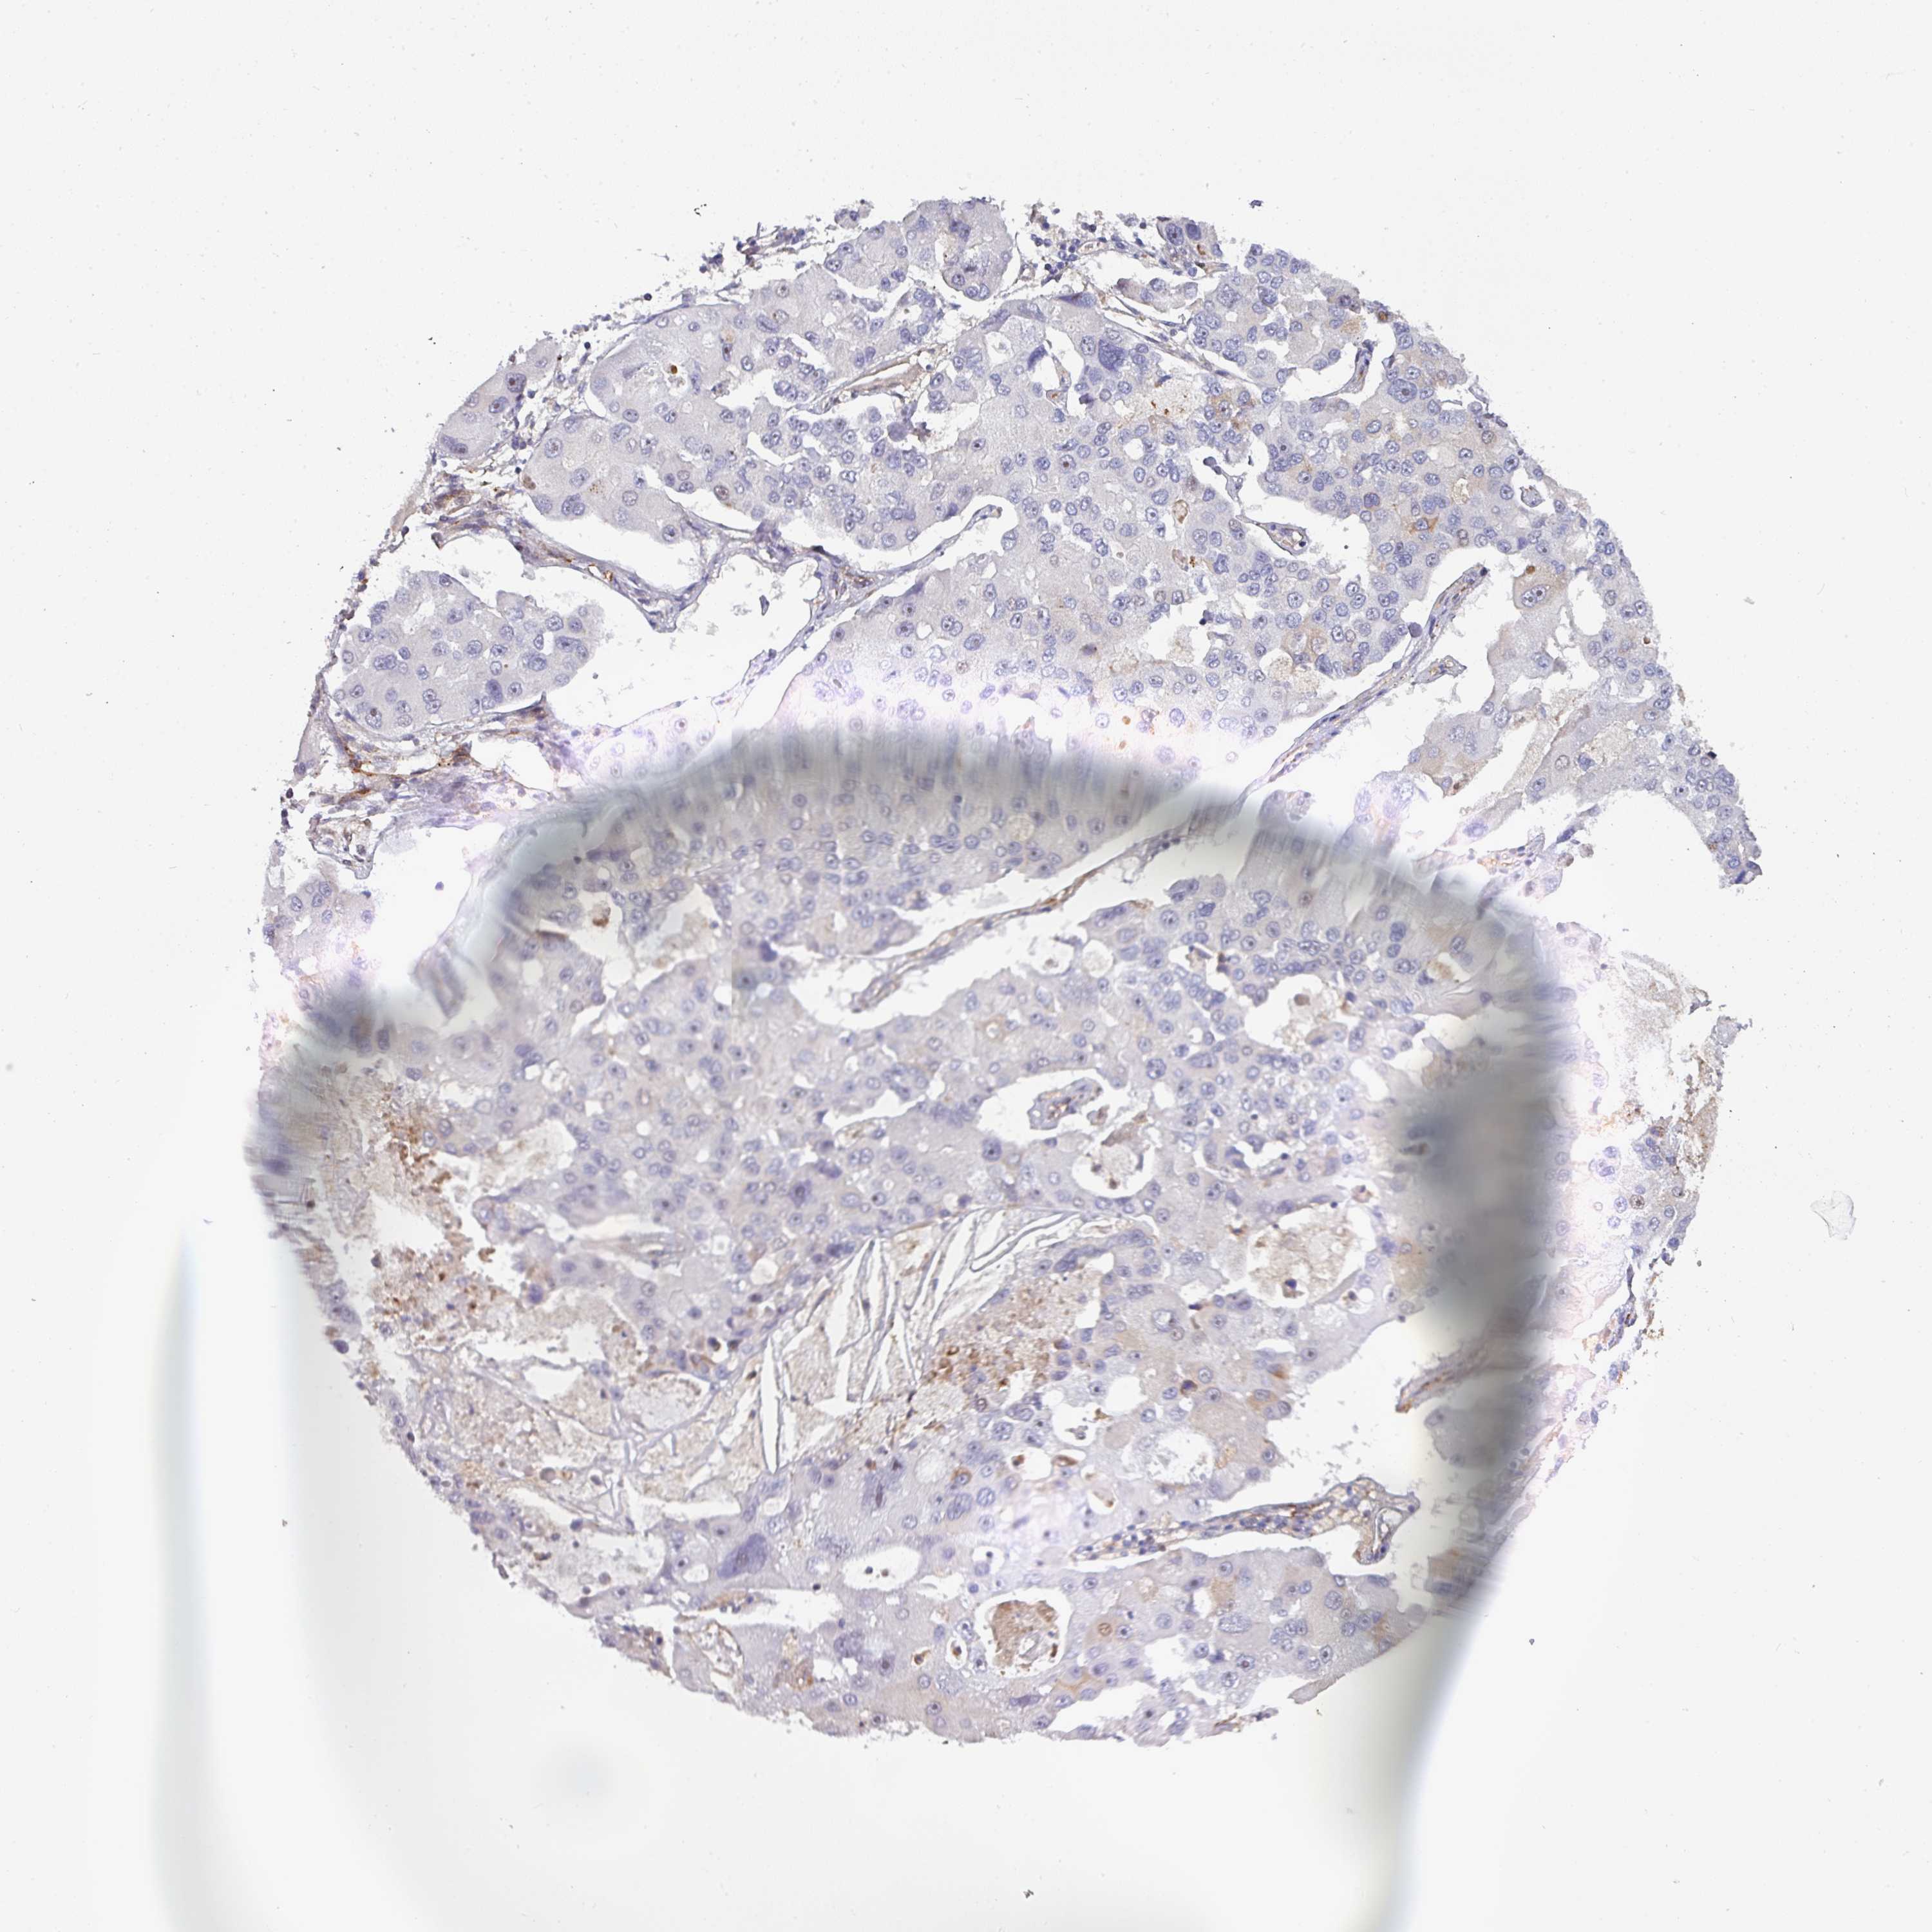

BEND5 is not prognostic in Lung Adenocarcinoma (validation)

LUNG SQUAMOUS CELL CARCINOMA (TCGA) - Interactive survival scatter ploti

BEND5 is not prognostic in Lung Squamous Cell Carcinoma (TCGA)